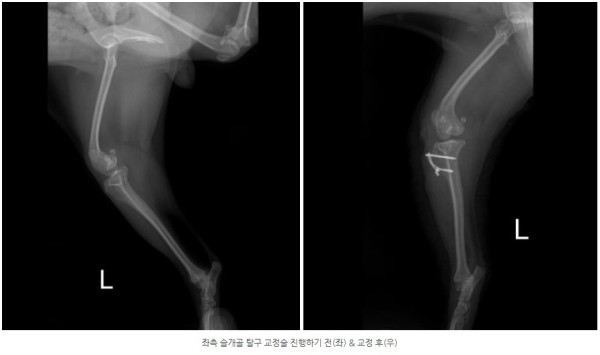

정확한 상태 확인을 위한 검사를 진행한 결과,

양쪽 모두 안쪽으로 슬개골이 빠지는 내측탈구 4기 상태가 확인되었고

통증의 근본 원인을 해결하기 위해 양측 모두 슬개골 탈구 교정술(MPL)을 진행하기로 결정하였습니다.